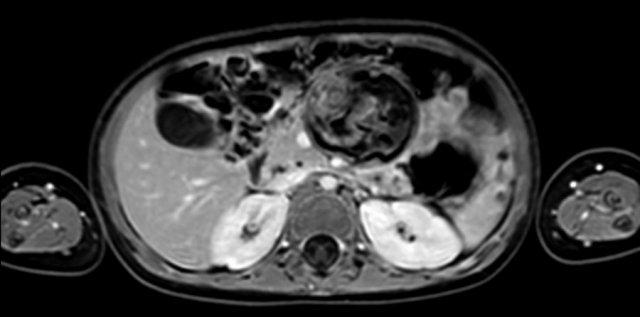

U nguyên bào thận ở thận trái của bé trai ba tuổi. Phần còn lại của thận trải dài trên khối u (dấu hiệu “móng vuốt” mũi tên). Khối u khá đồng nhất với một số vùng nang.

U nguyên bào thận ở thận trái của một bé trai ba tuổi. Khối u thùy đôi nằm ở vùng cực giữa. Có một đài thận giãn ở cực trên (mũi tên).